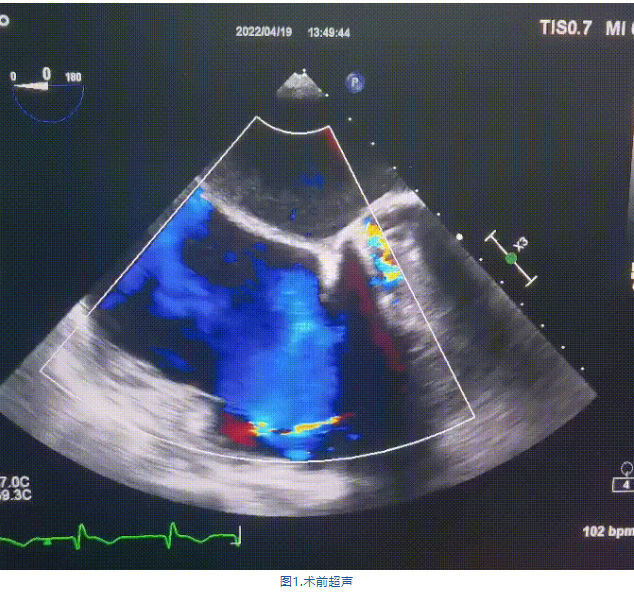

此次手術(shù)在全麻下進(jìn)行,采用經(jīng)右側(cè)頸靜脈入路。術(shù)中在經(jīng)食道超聲和DSA的指引下多個維度精細(xì)調(diào)整輸送器角度,在達(dá)到正確位置后,逐步釋放瓣膜錨定裝置和盤片,最終完成瓣膜植入。術(shù)后患者右房壓明顯下降,術(shù)后超聲提示人工三尖瓣同軸性良好,瓣架固定牢靠,無反流和瓣周漏,血壓術(shù)后即刻上升20mmHg左右,手術(shù)后監(jiān)護(hù)室順利拔除氣管插管,3天后恢復(fù)良好,予以出院。